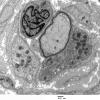

PERIPHERAL NEUROPATHY

18 HEREDITARY DISORDERS

Charcot-Marie-Tooth 1 (CMT-1) (3)